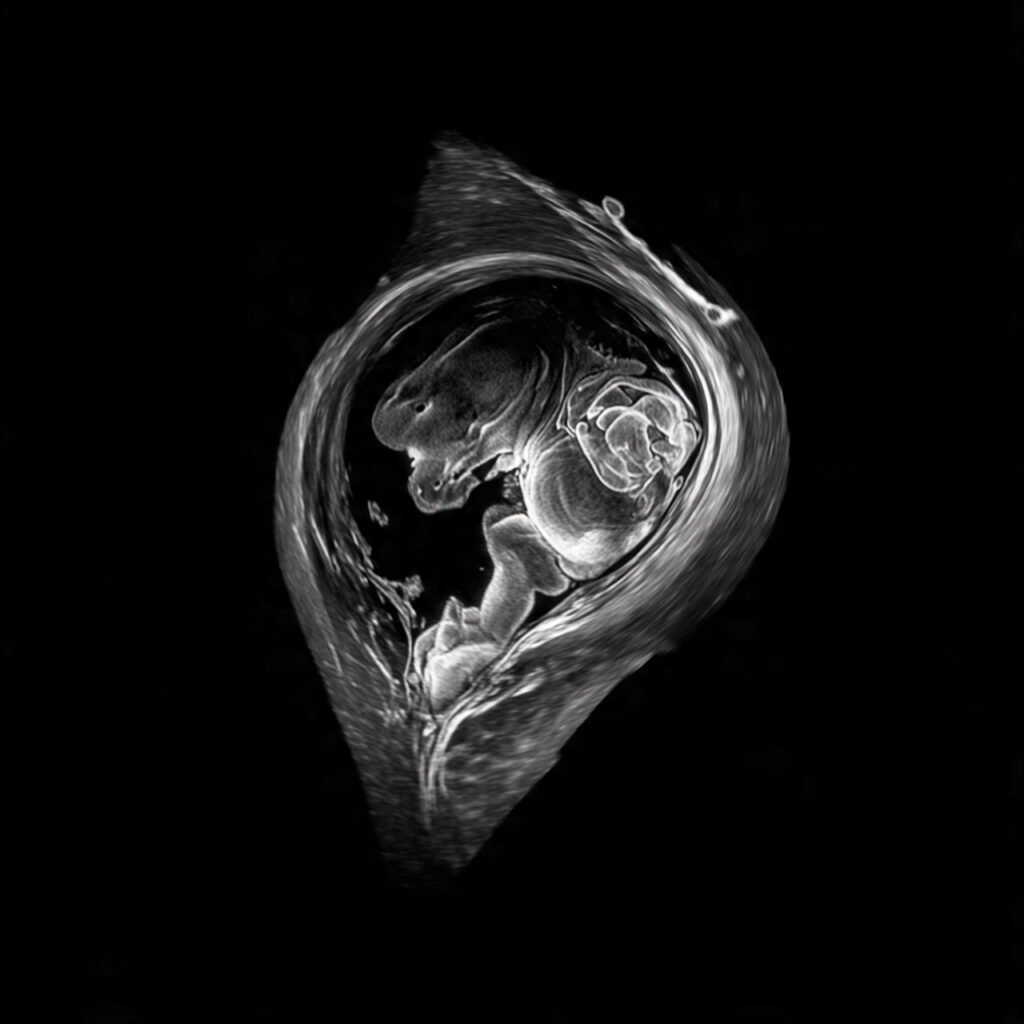

Founder of Nisarga Diagnostics, is a renowned fetal ultrasound specialist with over 20 years of expertise. An alumnus of Government Medical Colleges in Mysore and Bangalore, he also holds a D.N.B. from the National Board of Examinations, Delhi, and certification from the Fetal Medicine Foundation, London. A former Professor and HOD, he has trained countless PG students and junior radiologists, shaping the future of fetal imaging in India.